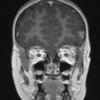

DEVELOPMENTAL MALFORMATIONS

Meningioangiomatosis (3)